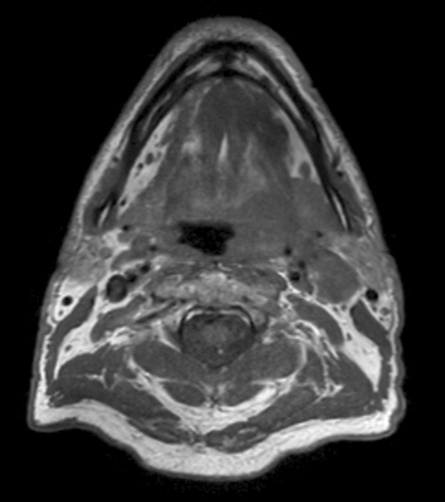

T1w TSE mDIXON (water only) pre contrast

A 75-year-old male with oropharynx squamous cell carcinoma in the left tonsil region with extension into the soft palate, caudal border lower tonsil region, no midline crossing. On the left side in the neck there are also three enlared lymph nodes on level 2 and 3 with central necrosis and signs of limited extracapsular extensionn, T2N2b. Patient underwent MRI simulation in the radiotherapy (5-point) positioning mask in Ingenia MR-RT 3.0T using the Flex coils in combination with integrated Posterior FlexCoverage coil.